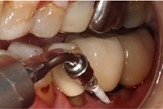

Au stade de « péri-implantite » il s’agit d’une atteinte inflammatoire des tissus mous entourant un implant. Le diagnostic clinique comprend un saignement au sondage, avec une suppuration quasi systématique, et une profondeur de poche péri-implantaire supérieure ou égale à 5 mm. Radiographiquement, un aspect radioclair de déminéralisation osseuse marginale supérieure ou égale à 2 mm entoure une partie plus ou moins étendue du corps de l’implant (fig 1 et 2).

Figure 1: suppuration au sondage d’une molaire atteinte de péri-implantite